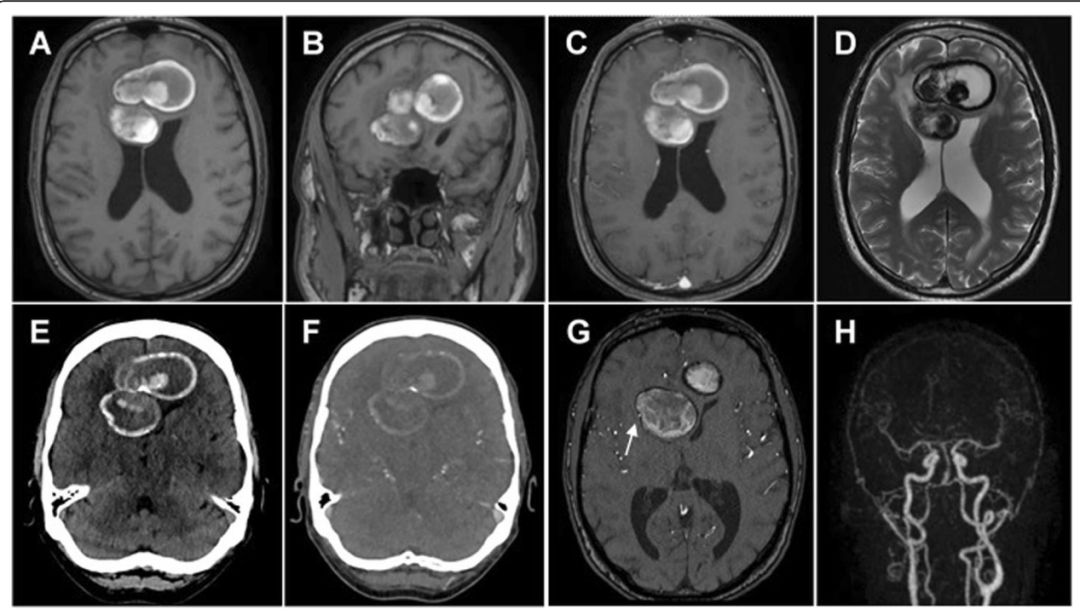

61岁,男性,右腿间歇性无力,轻度头痛(全脑),进行性认知功能障碍和嗜睡;血液及脑脊液检查无感染证据,无肿瘤细胞。

答案:巨大动脉瘤伴瘤内完全血栓形成。

本病例较难,在文献中也是通过手术才得到确诊。东非逗留个人史+脑脊液囊虫抗体滴度(1:20)最初诊断考虑脑囊虫病。术中诊断:左侧大脑前动脉巨大动脉瘤伴瘤内完全血栓形成,伴载瘤动脉血栓形成(原因可能为部分血栓形成的动脉瘤不断增长或血栓的逆行扩散而使母血管受压)回顾分析:MRI双侧额叶巨大肿块,T1WI病灶新月形高信号;T2WI病灶内无血管流空影,灶周水肿;CT平扫高密度肿块伴部分壁钙化伴少许瘤内出血;注射对⽐剂后未见明显强化(载瘤动脉血栓形成导致造影剂无法进入)导致误诊的主要原因。

巨大颅内动脉瘤(giant intracranial aneurysm)生长过程:自发性血栓形成→缓慢生长形成占位效应,破裂形成SAH。巨大动脉瘤腔内完全血栓形成事实上非常罕见。颅内动脉瘤伴血栓形成CT特征是环状强化,囊壁环状钙化,管腔内混杂高密度,可见靶征。MRI特征包括“洋葱皮征”,肿块内血管流空影,T2WI的瘤周水肿,病灶明显强化。总而言之,首先颅内球形肿块伴病灶内出血和壁钙化,鉴别诊断需考虑完全血栓形成的GIA;其次颅内球型肿块未出血、未钙化需鉴别颅内巨动脉瘤。